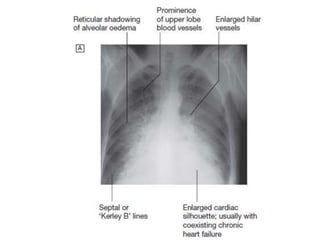

Figure 11.35 Chest X-ray in acute left ventricular failure:

is prominent alveolar pulmonary oedema in a perihilar (‘bat’s-

wing’) distribution. Note the bilateral pleural effusions.

Figure 11.35 ChestX-ray in acute left ventricular failure: the patient had severe pulmonary oedema caused by acute myocardial infarction. The heart is not yet enlarged, but there is prominent alveolar pulmonary oedema in a perihilar (‘bat’s- wing’) distribution. Note the bilateral pleural effusions.